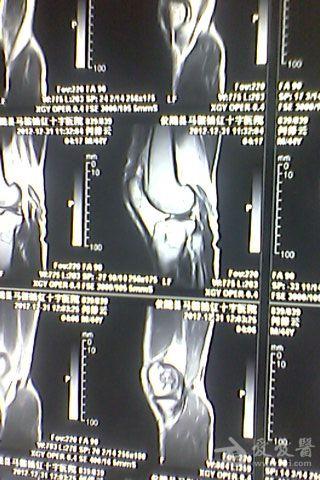

骨梗死影像表现

图片尺寸960x720